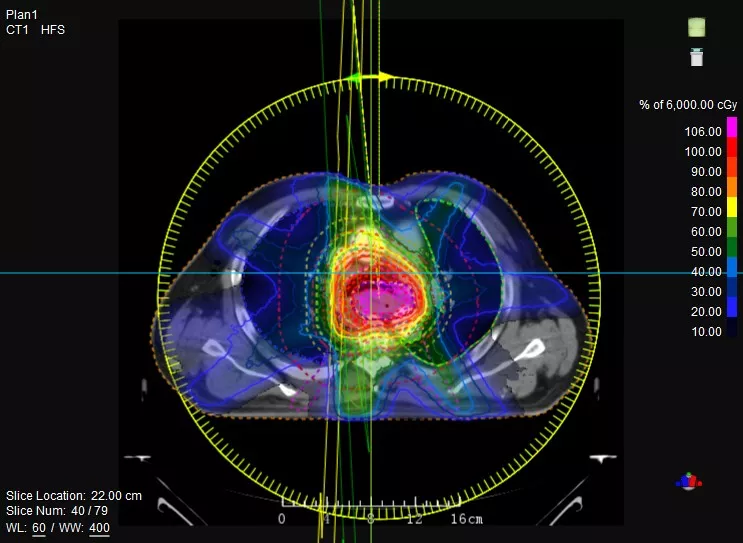

機載CT影像可直接用于放療計劃制作

鼻咽癌患者,進行旋轉容積調強治療(uARC)